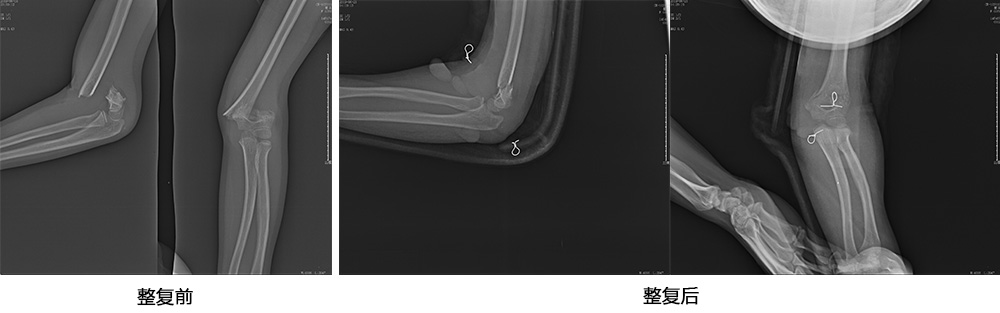

傳統(tǒng)手法整復(fù)病例影像